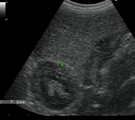

腹部エコー所見。胆嚢壁の肥厚(7.2mm)と中央の不動性胆泥。胆嚢粘液嚢腫と臨床診断した。 術中所見。胆嚢は暗赤色で固く拡大していた。直接生食を注入し総胆管を開通させた。 切除胆嚢所見。胆嚢壁は黒色粘液状物で裏打ちされ、内部に黒色の胆泥が凝縮されていた。 胆嚢の病理組織所見(強拡大)。胆嚢上皮は大部分が壊死・脱落していた。

経過:受診時、体温:37.2℃ 心拍数:66/分。可視粘膜蒼白。腹圧痛ないが熱感あり。CBCおよび血液生化学検査にてPCV42%, GPT>1000IU/L, ALP>3500IU/L, TBIL0.7mg/dl, GGT290IU/L, 腹部エコー検査にて胆嚢壁が中等度のエコー原性を示しながら著しく肥厚し(7.2mm), 中央の胆泥は体位を変化させても動かなかった。胆嚢粘液嚢腫が疑われた。ただちに胆嚢摘出術を実施することになったが、ACTが計測不能なほど延長しており(>1320秒)、手術適応不能であった。しかし、ビタミンK2の大量非経口投与を行い翌日のACTは129秒、他の凝固能検査でも正常値を示した。また2日間の強肝、輸液療法により起立し歩行する状態にまで状態が改善したので、その日輸血を行いながら手術を施行した。胆嚢を肝葉より剥離したところ、表面は暗赤色を呈し直径3cm位にまで大きくなりクルミのように固くなっていた。試験穿刺を試みたが液状物はまったく吸引されなかった。総胆管の開存性の確認は、体格が非常に小さく総胆管周囲のアプローチは困難であったので胆嚢周囲をガーゼで覆い胆嚢底から25Gの注射針を介して10mlの生食水を強い圧で注入して行ってみた。注入当初は非常に抵抗あったが、2ml程度注入しやや胆嚢が拡張してきてから突然抵抗がなくなり、10ml全てが注入され、総胆管の疎通性が確保された。その後、胆嚢管を結サツし胆嚢を切除した。その他の肝疾患の鑑別のため肝生検も行っておいた。術後、胆嚢を切開してみると、暗赤色の胆嚢壁は厚さ5mm程度の黒い泥状の粘液状物で裏打ちされ、その中心には弾力ある固さの黒色の胆泥が凝縮していた。胆嚢内容物を好気・嫌気培養検査に供したが細菌は検出されなかった。病理組織検査では急性化膿性胆嚢炎、すなわち胆嚢粘液嚢腫と診断された。内腔に大量の粘液を貯留し、胆嚢上皮は大部分が壊死・脱落していた。胆嚢壁は全層性に炎症が波及し、ヘモジデリンを貪食したマクロファージの集ゾクや各種炎症細胞浸潤と線維化が顕著に認められた。肝組織の方では、肝小葉がよく保たれ、胆嚢からの上行性の炎症波及による慢性肝障害がみられたに過ぎなかった。経過はきわめて良好で、術翌日よりよく歩くようになり食事も積極的に食べるようになった。術後4日後、全身状態は良好, GPT338IU/L, ALP2084IU/L, GGT 80IU/Lと確実に減少し、退院となった。